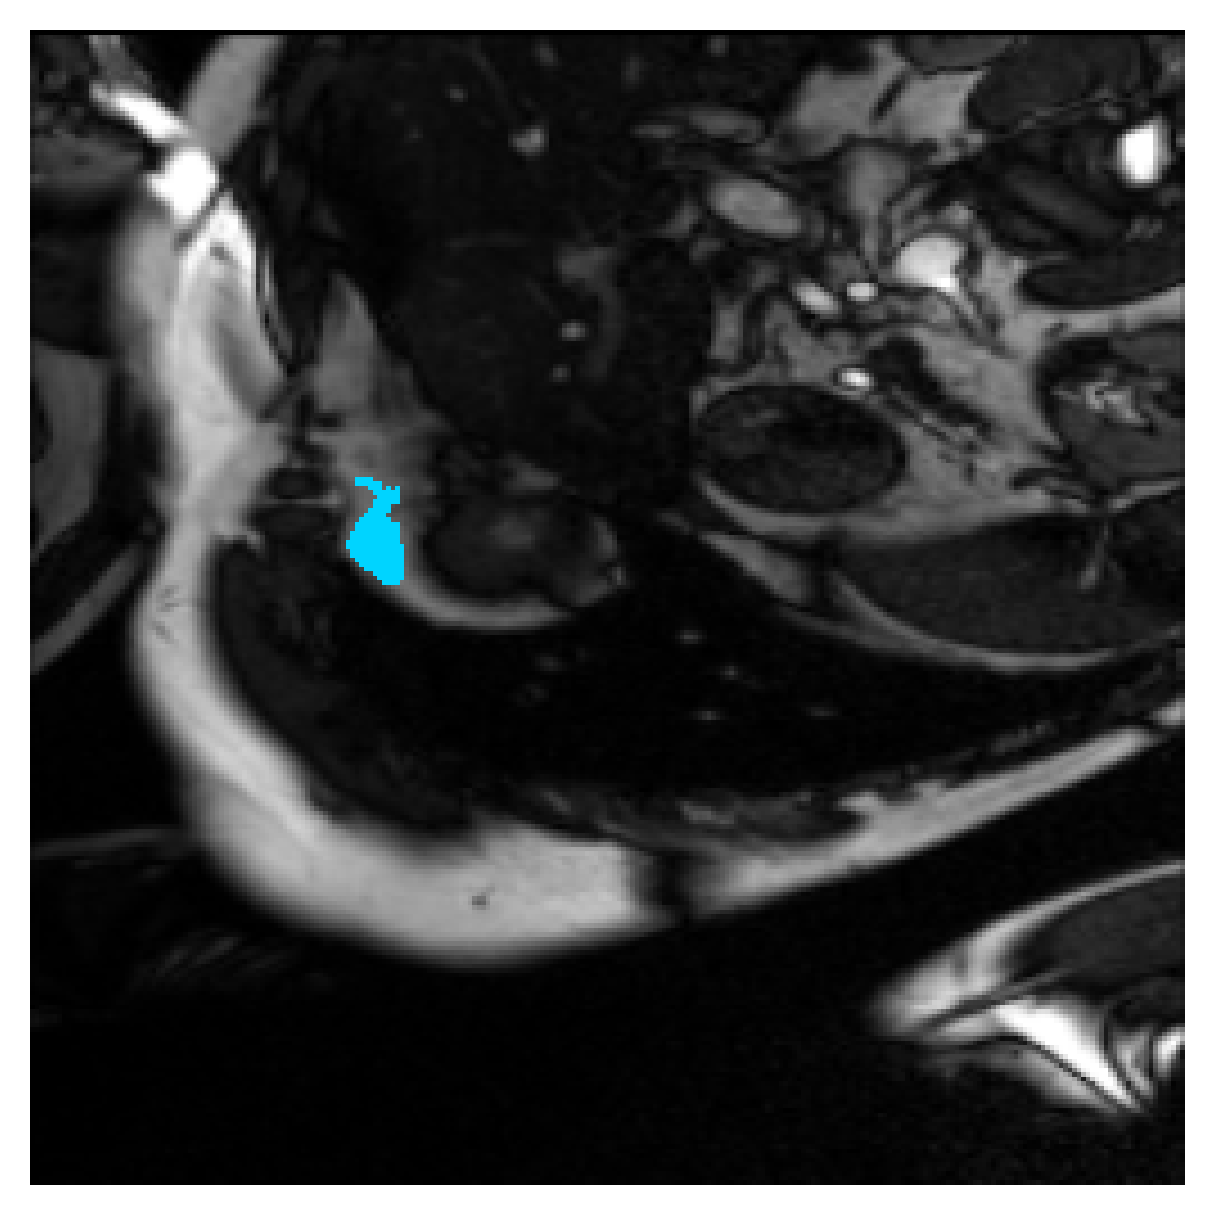

We normalize the volumes and resize the slices to pixels. As the official dataset comes with full annotations, we create a synthetic point ground truth. This is done by first randomly choosing the centers of the point annotations within the class masks, followed by filling an ellipse with axes lengths of and (in pixels) around each center. The intersections of these elliptic discs with the underlying full annotations are then used as our point ground truth. See Figure 2 for an example of the created weak annotation mask. The point annotations are created for every slice, one for each foreground object present in the slice.

| (a) Ground truth | (b) , full | (c) , weak | (d) |

| (full) | supervision | supervision | |